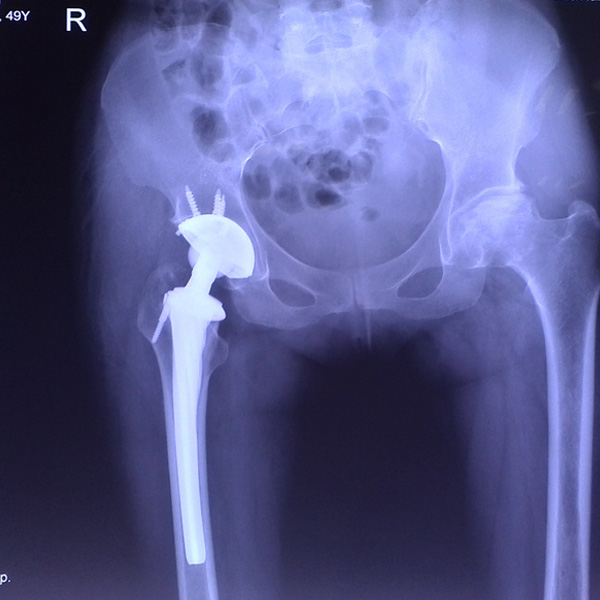

右側全髖關節置換

患者姜某某,女50歲,診斷為“股骨頭壞死”,右側髖關節疼痛到不能生活自理。經平臺推薦到哈爾濱醫科大學附屬第二醫院骨關節科就診,患者想......